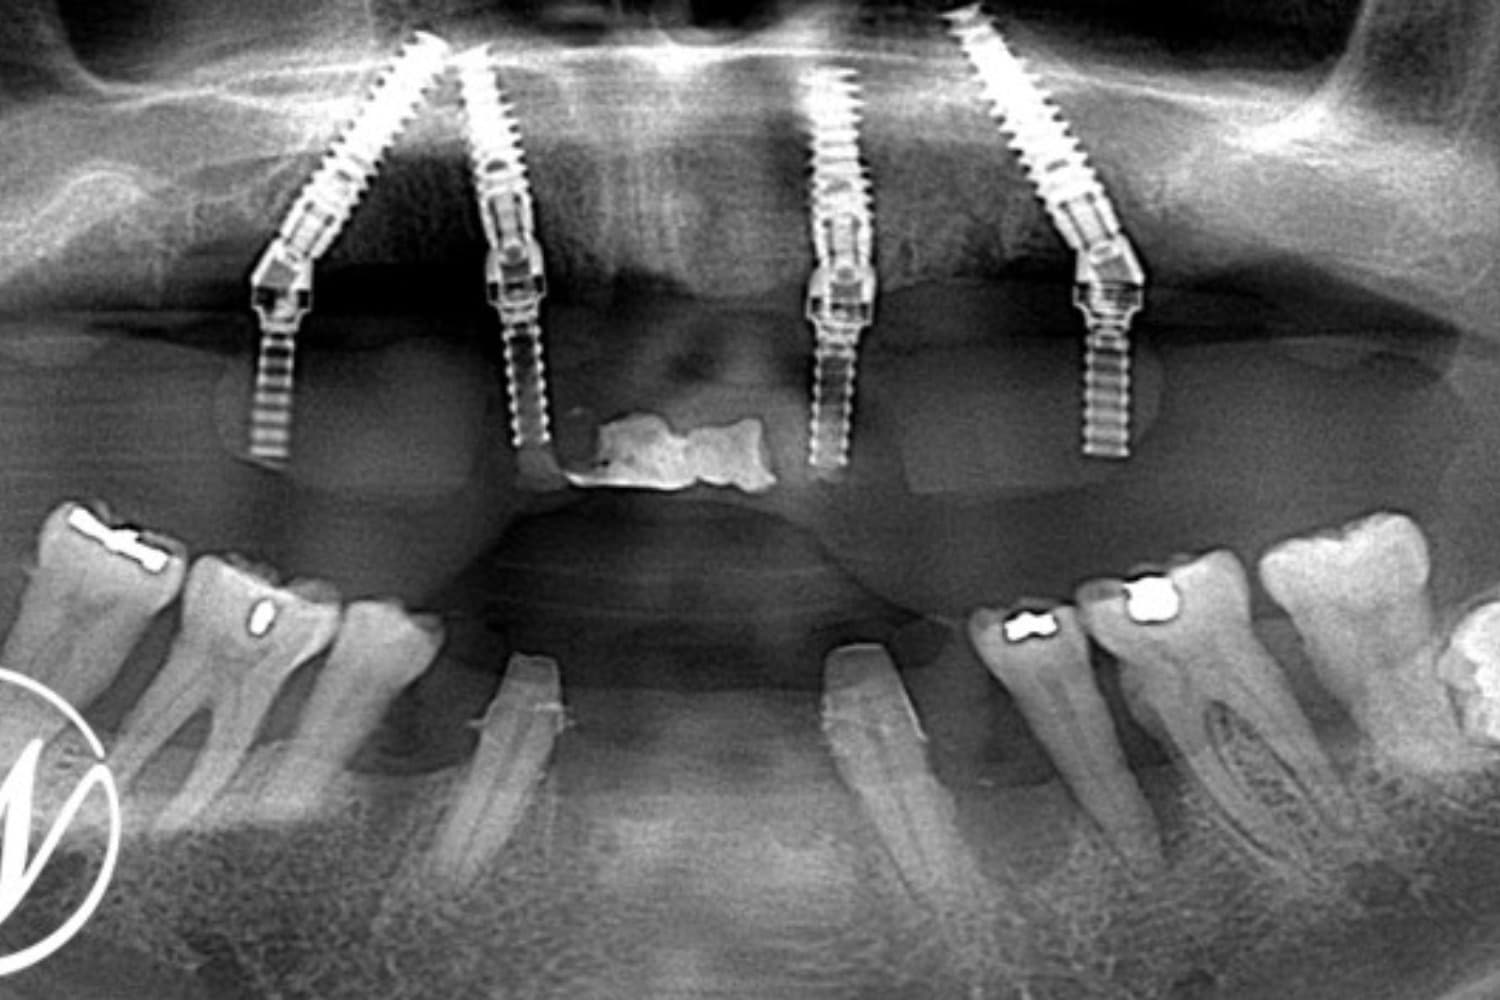

After

下顎前歯部:抜歯後に仮歯付きブリッジを装着 上顎全体:オールオン4によるインプラント治療を選択 治療内容 治療当日に仮歯を装着し、審美性を即日回復 治療期間の短縮と出張スケジュールへの配慮 鎮静下(静脈内鎮静)でのオペによる痛み・恐怖の軽減 オペ前日 下顎前歯部を抜歯 仮歯付きのブリッジを装着。下顎前歯の突き上げを排除 オペ当日(上顎) 鎮静下にて残存歯をすべて抜歯 オールオン4の術式でインプラント4本を埋入 その日のうちに仮歯を装着し即時荷重(審美性をその日に確保)

準備期間:約1ヶ月(※通常2ヶ月) インプラント埋入〜最終補綴:約4〜6ヶ月

6回

税込み¥1,500,000

・即時荷重を行っているため、術後の食事制限(硬い物・熱い物・粘着性のある物の制限)が必須 ・食事制限を守らないとインプラントが骨と結合せず、ロスト(脱落)のリスクがある 骨量が十分でない方や歯ぎしり・食いしばりの強い方には適応できない場合もある